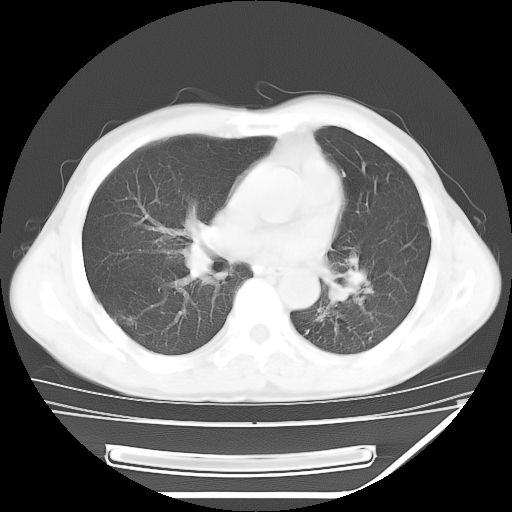

男,59岁,“结核性胸膜炎”30余年,胸部经常疼痛,多次x检查提示“肺部”炎症。腹部疼痛5日,b超提示:“肝内短管结石,余显示不清,建议进一步检查。”

两肺结核并右侧胸腔积液;脾脏、腹腔及腹膜后淋巴结结核[陈旧性];肝内胆管结石

胸部腹部都是结核(双肺。纵隔淋巴结,肝脏,脾脏,肠系膜)